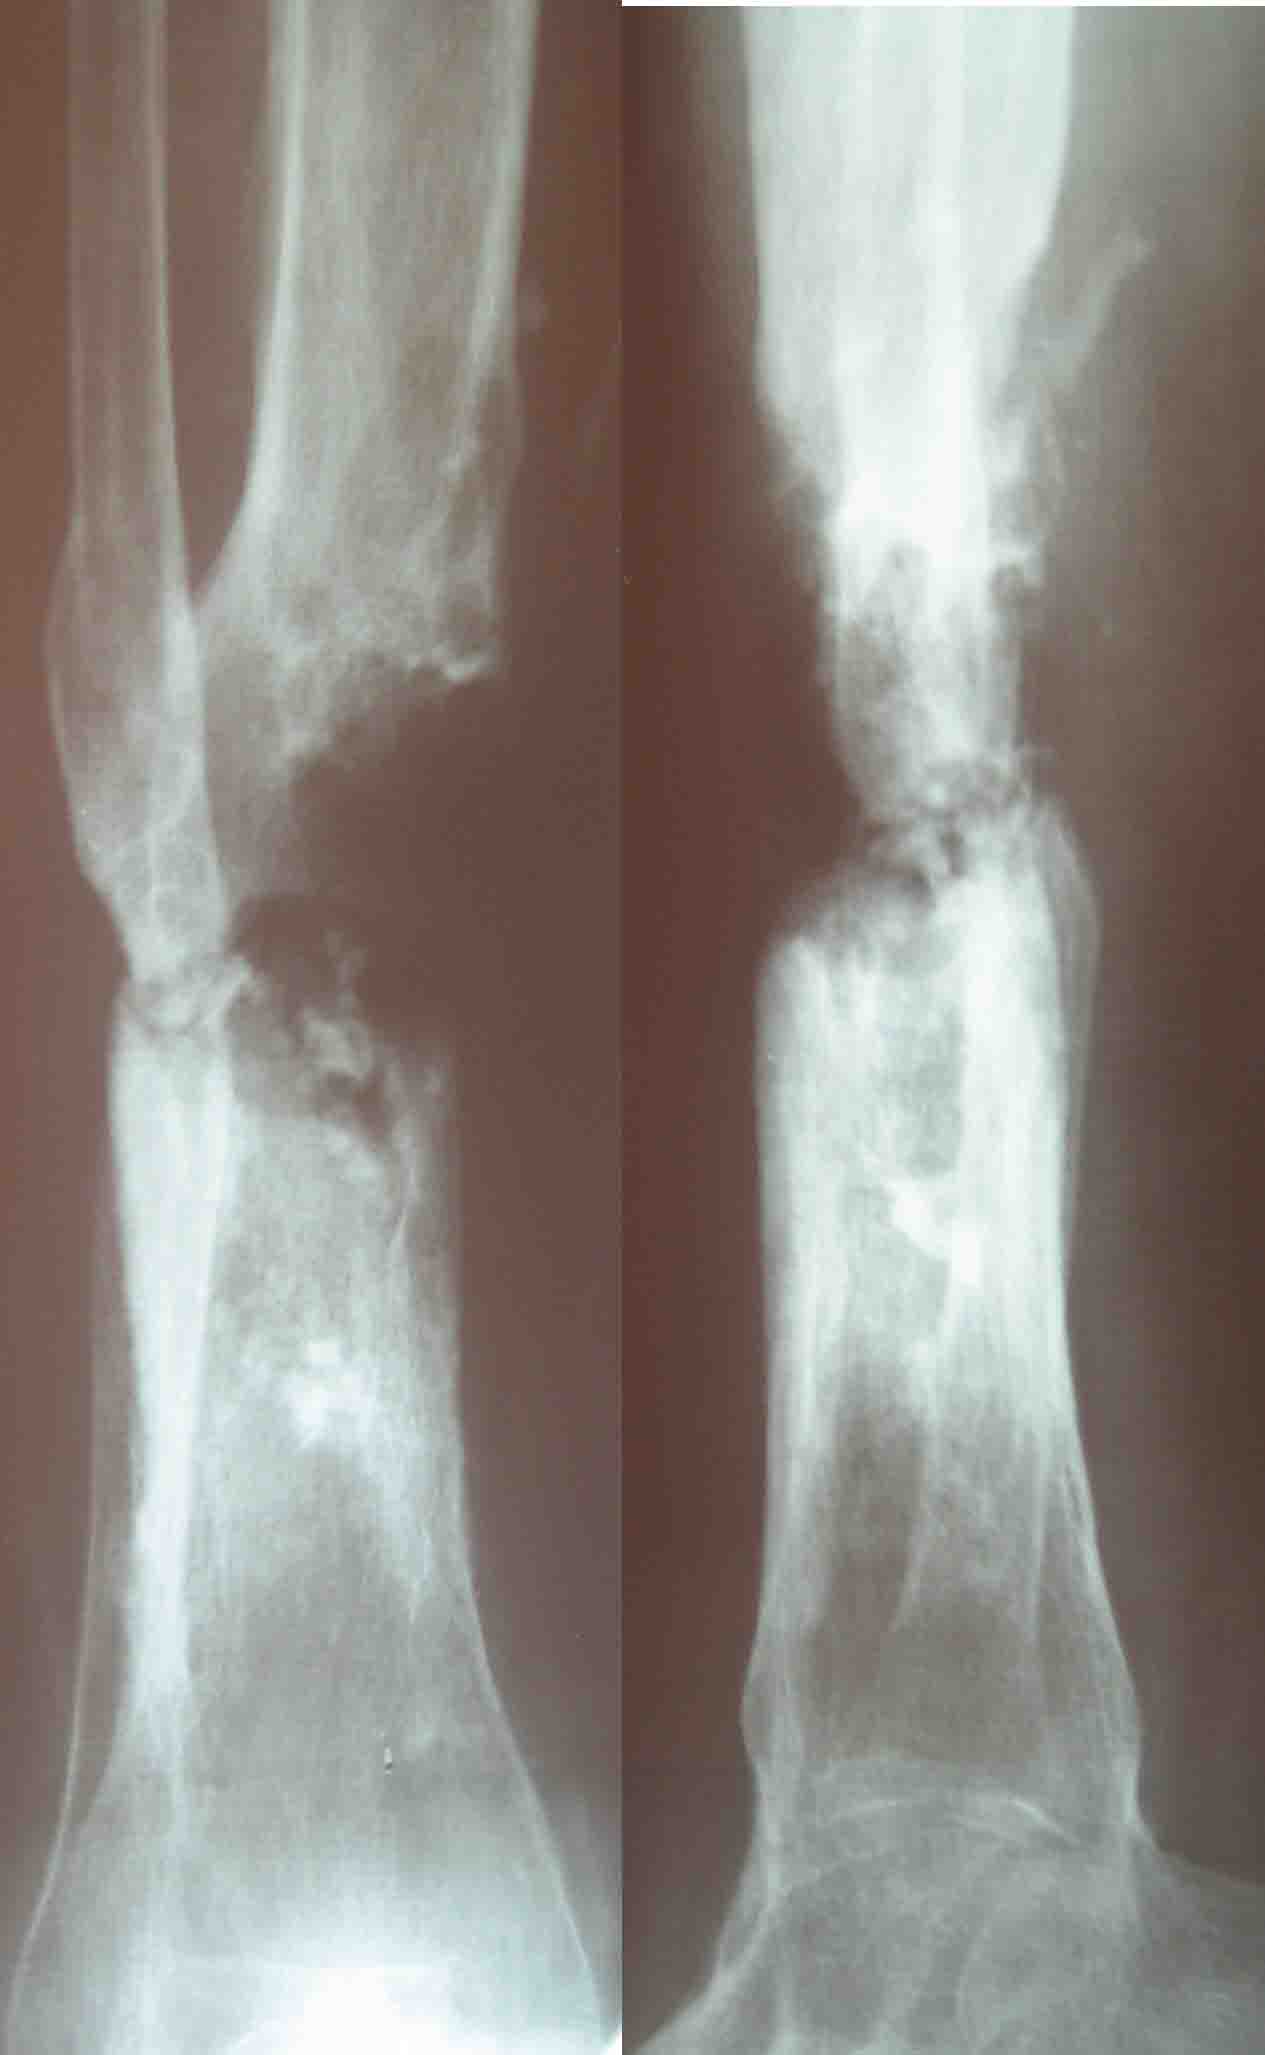

Кратко: мужчина за 60 лет получил травму 28 лет назад (переехало

автобусом). Оперировался десятки раз, в итоге с очередным

патологическим переломом, хронической язвой и гипсовой лонгетой попал

ко мне... Объективно - остеомиелит, инфицированный ложный сустав (или

как его назвать), остеосмиелит, флегмона по наружной поверхности

голени, укорочение около 5 см.

На операции резекция 8 см, внешний остеосинтез,одновременное сближение

примерно на 4 см, а затем постепенное сближение до полного контакта в

течение 3 недель. Рана с патологически измененными краями, имевшая на

операции размеры примерно 4-5 на 10-12 см закрылась самостоятельно в

течение примерно 2-х мес. Ну не самостоятельно, конечно, а с нашей

помощью, но без пластики.

Сейчас в аппрате вытянул около 6 см в верхней трети.

Имя     : Рентген до операции.jpg